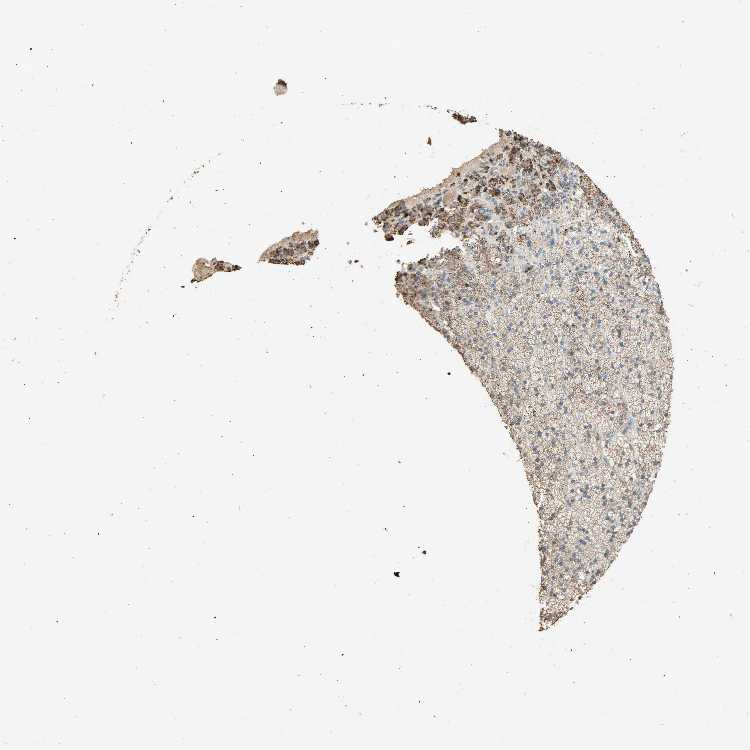

ADRENAL GLAND - Antibody stainingi

Antibody staining in the annotated cell types in the current human tissue is reported as not detected, low, medium, or high, based on conventional immunohistochemistry profiling in selected tissues. This score is based on the combination of the staining intensity and fraction of stained cells.

Each image is clickable and will lead to virtual microscopy that enables deeper exploration of all samples and also displays staining intensity scores, fraction scores and subcellular localization as well as patient and tissue information for each sample.

Antibody HPA003014Antibody HPA003060Antibody CAB004997

Glandular cells LowLowMedium